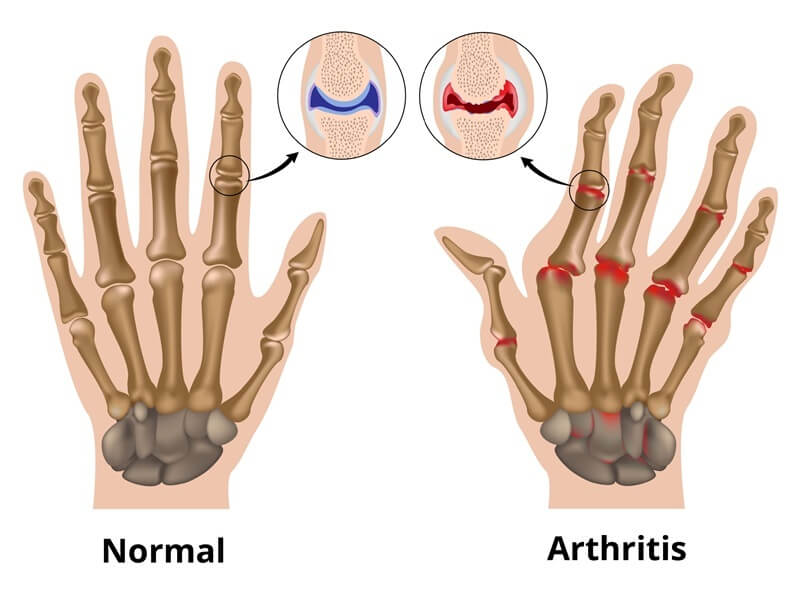

What Is Arthritis?

“Arthritis is the swelling and tenderness of one or more joints. The main symptoms of arthritis are joint pain and stiffness, which typically worsen with age. Some types of arthritis happen after injuries that damage a joint.

Painful joints and stiffness not only restrict movement, but also signify internal inflammation. It is a painful disease that can cause ordinary tasks like picking up a cup of coffee or walking up the stairs turn into a struggle.”